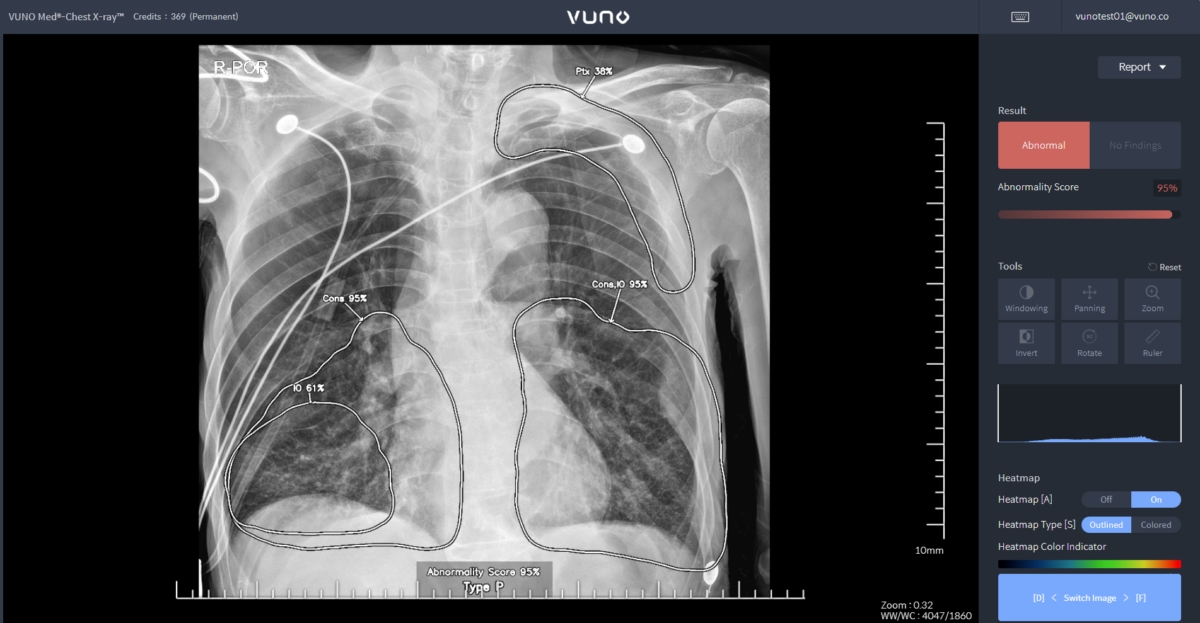

Chest X-ray는 흉부 X-ray 영상을 분석해 5개의 이상 소견(결절, 경화, 간질성 음영, 흉막 삼출, 기흉) 유무를 검출한다. 폐렴과 폐결핵 선별도 가능한 진단 보조 소프트웨어이다. 혁신의료기술 고시에 따라 6월부터 3년간 임상 현장에서 사용할 수 있으며, 의료기관은 비급여 청구가 가능하다.